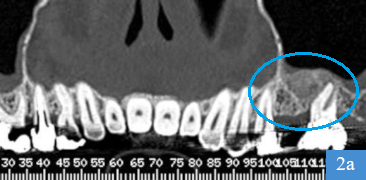

coupe panoramique de dentascanner, 4 mois après la greffe osseusecoupe coronale de dentascanner, hauteur osseuse de 12 mm

Dentascanner 4 mois après la greffe

2a : greffon osseux visible, positionné à l'endroit où il manquait de la hauteur d'os

2b : os sous le sinus mesuré à 12 mm de hauteur ; pose d'un implant possible